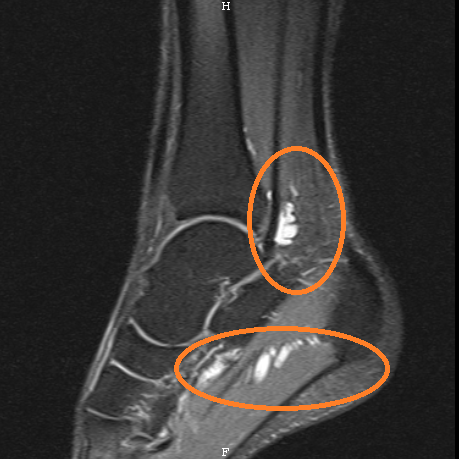

Habe nun die MRT Bilder angehängt. Darauf sieht man ganz deutlich die Wassereinlagerung um die Hallucis Longus Sehne, in der Fusssohle und auf der Höhe des Achillessehnenansatzes.

Eine Frage an die Experten hier

: Ist es möglich die Wassereinlagerungen/Entzündungen rauszusziehen oder durch Injektionen zu beseitigen (Ich weiss: kein Cortison spritzen).

Mir als Laie haben die beiden MRTs keinerlei Aufschluss gegeben, er hat aber nur direkt gemeint: Er sieht zwar Entzündungen/ Wassereinlagerungen, aber nicht an der Achillessehne (die Achillessehne hat keinerlei Schäden gezeigt) sondern an der Hallucius Longus Sehne!!! D.h. 1 x Mal an der Fussohle und 1 x Mal auf der Höhe des Fersenansatzes.